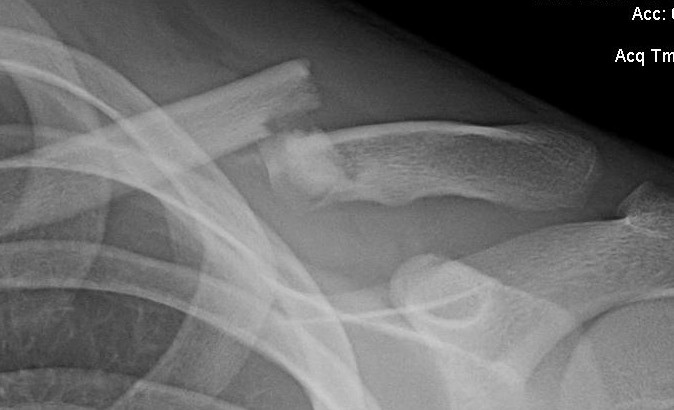

podobnoja Napisano 27 Maja 2014 Napisano 27 Maja 2014 Witam, Chciałem się podzielić, no i przede wszystkim ostrzec tych co nie uważają i nie szanują swojego zdrowia (w tym siebie)... Podczas złamania, leczenia szukałem wiele informacji na temat: złamania, jak długo itd. (postaram się wszystko opisać, nawet wstawić zdjęcia 1 marzec - lasek - szaleństwa -> upadek na prawy bark i stwierdzenie, że pewnie złamałem obojczyk. Pierwsze złamanie, dziwne mrowienie w okolicach barku, delikatny ból to wracam na rowerze z opuszczoną ręką do domu 8km... Zauwazyłem patrol policji chciałem podjechać, żeby pomogli mi (raz chciałem coś o tych...), co zrobili odjechali, obserwując mnie jakbym był jakimś debilem. Po 1km spotkałem jakoś Panią z dzieckiem i pomogła mi założyć plecak bo mi się wkręcał w szprychy... Dojechałem do domu, szybko wsiadłem w samochód i pojechałem na pogotowie.... .... .... czekałem .... .... .... 6h łącznie ze złamanym obojczykiem, wiadomo standardowa procedura (wizyta -> zdjęcie -> czekanie -> wizyta -> gips), wtedy w szpitalu w Poznaniu, ładowali hurtowo w gipis... Potem dowiedziałem się to był stażysta, chyba który się uczył (s######y... na mnie i na wielu innych). W gipsie wróciłem samochodem, ledwooo, nie mogłem wrzucić 1 biegu, ale na szczęście była, że mną moja kochana dziewczyna, która przez ten cały okres była dla mnie najbardziej pomocą osobą... Po 2 dniach zapisałem się do ortopedy, oczywiście prywatnie, bo terminy w 15 placówkach były na maj... wiec mi się sam zrośnie obojczyk, prywatnie oczywiście udało się w ten sam dzien.... Lekarz zobaczył zdjęcie, obejrzał, sprawdził gips i powiedział: "Ku*** ten gips jest źle założony". Myślę sobie fajnie fajnie... Lekarz mi zalecił kupno ortezy ósemkowej: Nie polecam, po 3 miesiącach mam pamiątki po niej... Polski produkt jednak nie nadaję się do niczego i nie był wcale tani, 100 zł. Dobra wracają do tematu. Nosiłem ortezę do około 12 kwietnia, z cotygodniowym zdjęciem RTG. Były lepsze monety , że wyglądało całkiem spoko i gorsze. Po zdjęciu ortezy, dostałem skierowanie na tomografie komputerową. W tym przypadku podobnie jak z zapisami do ortopedy, nie jest łatwo, z dopiskiem na skierowniu "pilne" czekać trzeba miesiąc (poznań). Teraz miałem 20 maja tomografie, odebrałem zdjęcie i jak zobaczyłem ręce opadły.... Dzisiaj idę na kontrole, wydaję mi się, że na pewno wizyta będzie miła... jeśli doktor stwierdzi, że potrzebna będzie operacja, to się wkur***, że pozwoliłem zmarnować sobie 3 miesiące. Mimo, że obojczyk wygląda jak wygląda to mnie nie boli, nie czuje dyskomfortu. Podczas ruszania wydaję mi się że się rusza cały, nie tylko złamana część. Wiec jest to dla mnie dość dziwne, jak to możliwe... Na koniec dodam opis badania:"Stan po złamaniu odcinka środkowego obojczyka z przemieszczeniem, z odłamami pośrednimi. Brak zrostu. Brzegi odłamów sklerotyczne, wzdłuż powierzchni trzonu widoczne ciągłe odczyny okostnowe. Pogrubienie warstwy korowej" Nie wiem po co to napisałem... z nadzieją, że może ktoś pocieszy, że tak jak spora cześć ortopedów napisze: "że najważniejsze w złamanym obojczyku jest odtworzenie jego długości, a że krzywo to mało ważne".... Znacie może jakiś dobrych specjalistów w Poznaniu?

podobnoja Napisano 27 Maja 2014 Autor Napisano 27 Maja 2014 Zgadzam się z Tobą: bo mi też wielu specjalistów powtarzało, że obojczyk zrasta się w 99% i nie musi prosto. Czas najlepszym lekarzem Podczas noszenia ortezy miałem regularnie zdjecia RTG i dociągania ortezy, dwóch lekarzy mi naciągali... musiałem się owijać bandażami elastycznymi bo nie było do wytrzymania... W ortezie aż nitki puściły wiec raczej noszenie jej było poprawne... Dzisiaj byłem u lekarz dać własnie tomografie komputerową (powyżej zdjęcie), za tydzień wizyta i stwierdzenie co dalej, chociaż powtarza, że jak się trzyma i nie boli to nic nie będziemy robić... A już od miesiąca żyje, zrobiłem z 500km na rowerze i on tak wygląda... Nie boli, nie próbowałem podnosić nic cięższe niż z 15 kg... Wydaję mi się, że on musiał się złapać, niby w programie do tomografii komputer wymierzyłem wszystko, kośc obojczyka 1,2cm, gdy na siebie nachodzą 2cm, wiec zaczym się obleje w 100% 2cm obwodu to trochę potrwa. Tylko martwi mnie ten kikut "ostry", mimo, że go nie czuje to on aż 1cm wystaję. A według mnie szacunkowy zrost to 1cm... wiec niby szerokość obojczyka Człowiek naprawdę jest w stanie dowiedzieć się wiecej, niż od lekarza. Każdę zdjęcie rtg studiowałem, teraz tomografie. Nie długo zostanę specjalistą